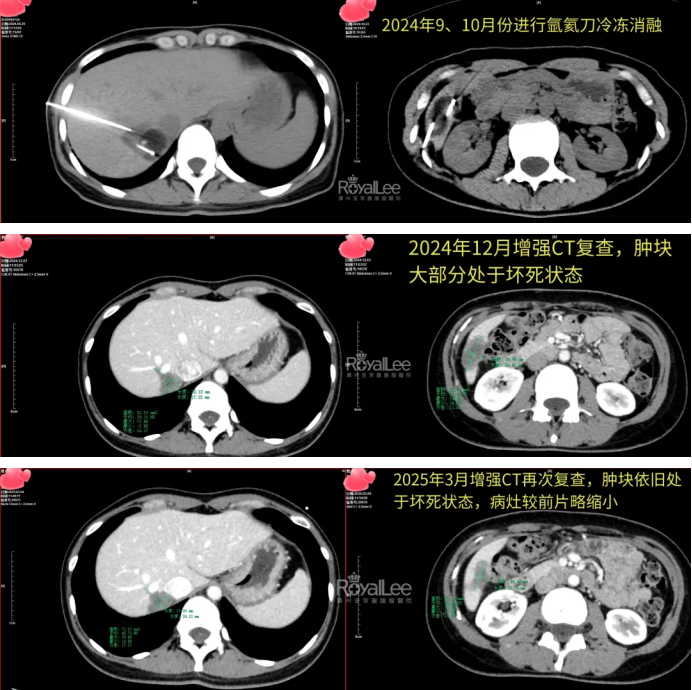

Huang Deliang, technical director of the Department of Minimally Invasive Intervention, and his team performed "CT-guided argon-helium knife ablation of secondary malignant tumors of the liver" on Ms. Ji in September and October 2024, and the operation went smoothly.

Excitingly, a follow-up examination two months later showed that most of the tumor had been necrotic. A follow-up enhanced CT scan in March of this year also showed that the lesion had shrunk.